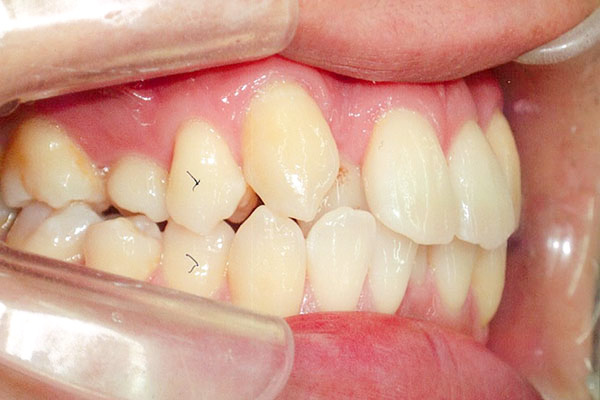

症状八重歯+二重歯列による噛み合わせ不具合

治療前